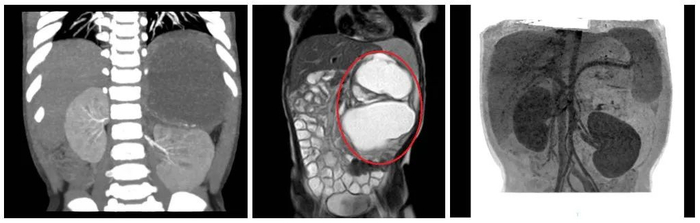

细心的妈妈赶紧带着她到柳城县妇幼保健院检查。B超结果显示,慧慧的肚子里长了一个约14cm×8.5cm×10cm的肿瘤,大小如同一个小苹果。

肿瘤占据腹腔大部分空间

需要尽快手术

“慧慧的肿瘤很大,已经占据了腹腔很多空间,如不及时处理,会压迫邻近脏器。如瘤体压近消化道会出现肠梗阻;推挤膈肌会出现呼吸困难;如与消化道相通时可出现瘘,瘤体还可发生感染引起感染症状。”

慧慧的小肚皮不过排球大小,而肚子里的肿瘤,几乎占据了腹部的大部分位置,把肠子都挤到了右侧腹部,把左肾挤到右下腹,把脾脏推向左上腹部。肿瘤周围遍布重要脏器及血管。